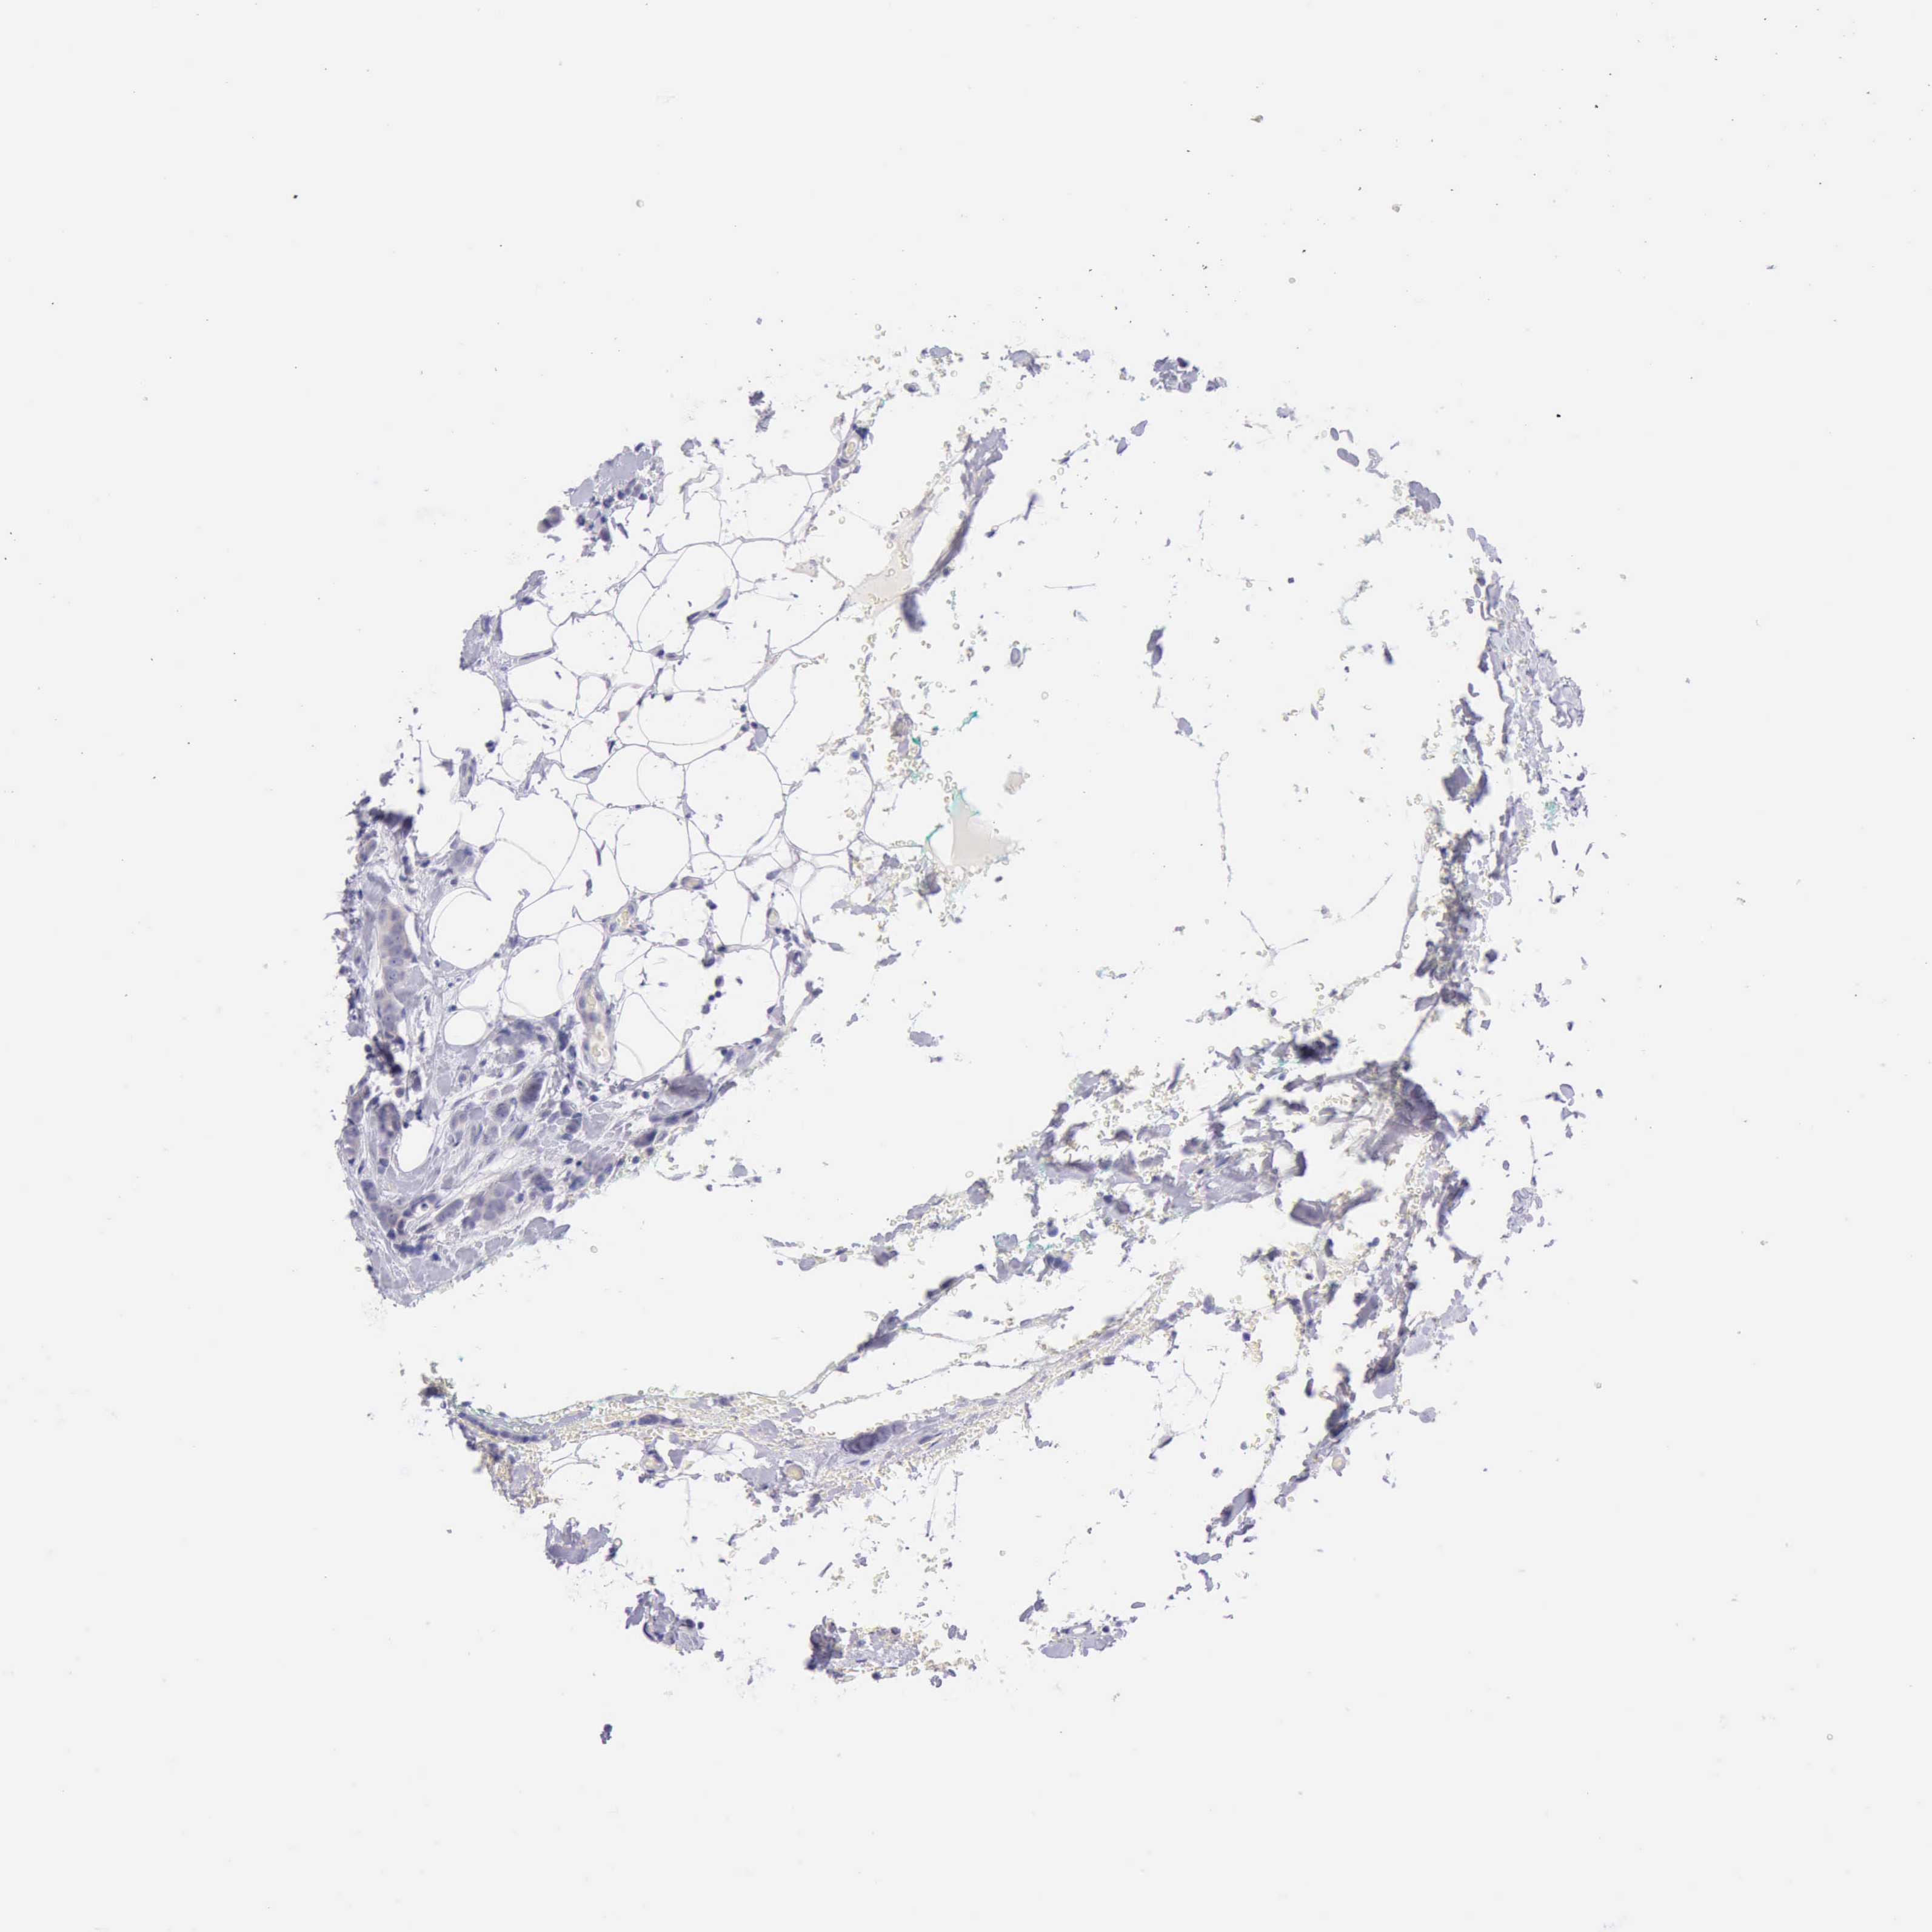

BRCA TCGA BRCA VALIDATION PROTEIN EXPRESSION

Breast cancer

Human cancer